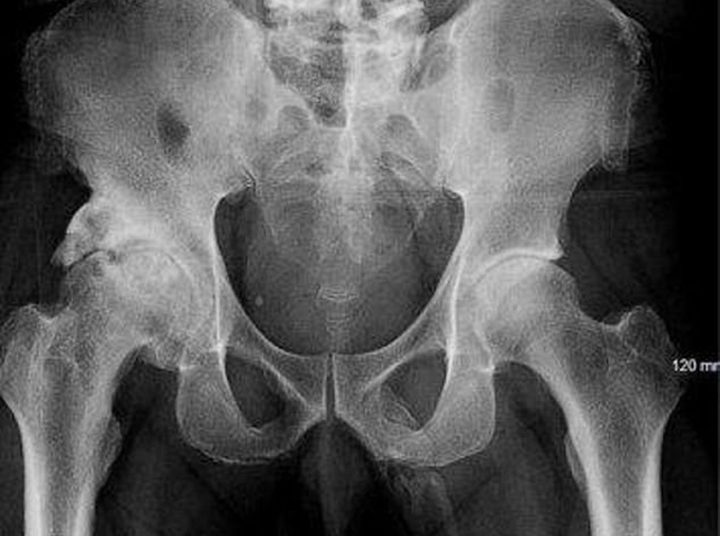

Durante la revisión médica, los doctores tuvieron que verificar el estado de su pelvis y que no tuviera huesos rotos pero encontraron algo raro.

Le dijeron que no tenía huesos rotos pero un hueso estaba creciendo en su pene, pero el hombre al parecer no contento con el diagnostico, se fue y no regresó.